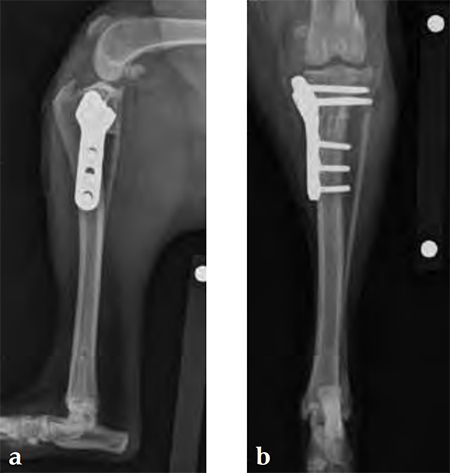

A 4-year-old, female, spayed, 33 kg English bulldog had a CrCL tear and a medial patellar luxation. The small stature 3.5 mm TPLO plate was perfect for this dog due to the small profile of the bone and the need to use a heavier plate (3.5 vs a 2.7 mm). In the past, veterinary surgeons have been forced to either squeeze the standard TPLO 3.5 mm plate on the bone or use an undersized TPLO 2.7 mm plate. In this patient, the shorter and smaller profile head of the small stature TPLO 3.5 mm was perfect.